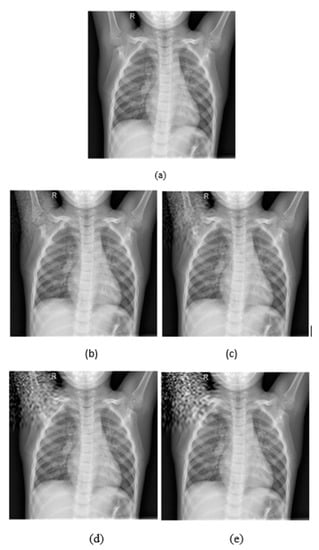

As it is shown in Figure 3a, the watermarking is embedded on the upper left corner, as the p parameters are equal to 0.1, while in (b) the watermarking was embedded on the bottom right corner because p values are equal to 0.9. Both p values range from 0.1 to 0.9 by representing all local points of the image. In Figure 4, it is presented how the embedding strength affects the distortion of an image while the other parameters are constant (L-bit = 1000, p1 = 0.1, p2 = 0.1), and in Figure 5 the perturbation is presented from L-bit length (embedding strength = 300, p1 = 0.1, p2 = 0.1). Embedding strength controls the limit of watermark information that is inserted in the image. A large embedding strength provides more robustness, but it is also more perceptible at the same time.

Figure 4.

(a) Initial image. (b) Embedding strength = 50, (c) Embedding strength = 100, (d) Embedding strength = 200, (e) Embedding strength = 300. The rest of the parameters are L-bit = 1000, p1 = 0.1, p2 = 0.1.

Figure 5.

(a) Initial image, (b) L-bit = 200, (c) L-bit = 500, (d) L-bit = 800, (e) L-bit = 800. The rest parameters are Embedding strength = 300, p1 = 0.1, p2 = 0.1.

As it is depicted in Figure 4, increasing the embedding strength the quality of the image is getting worse and the noise becomes more perceptible and intense. On the other hand, in Figure 5 the intense of the noise is almost the same in all L-Bit lengths, but it changes the magnitude of the noise.